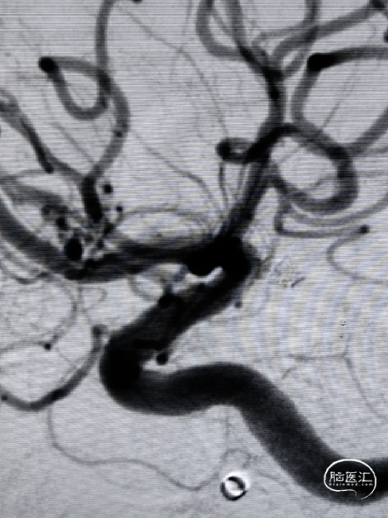

左侧颈内动脉造影

右侧颈内动脉造影

双侧椎动脉造影

压颈造影及压颈3D